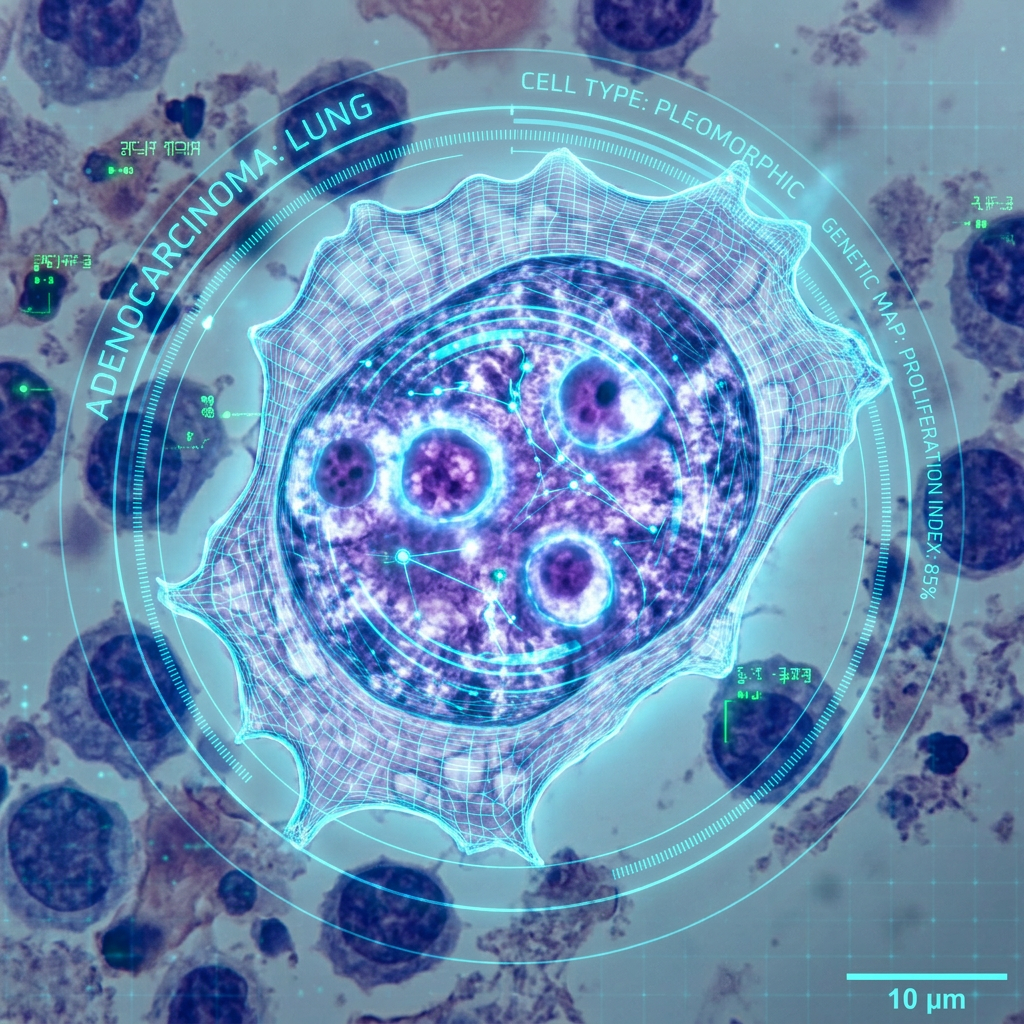

Precision Medicine Lung Cancer Tumor Board

Join host Charu Aggarwal, MD, MPH, Penn Medicine and guest panelists every other Tuesday at 8:30pmET